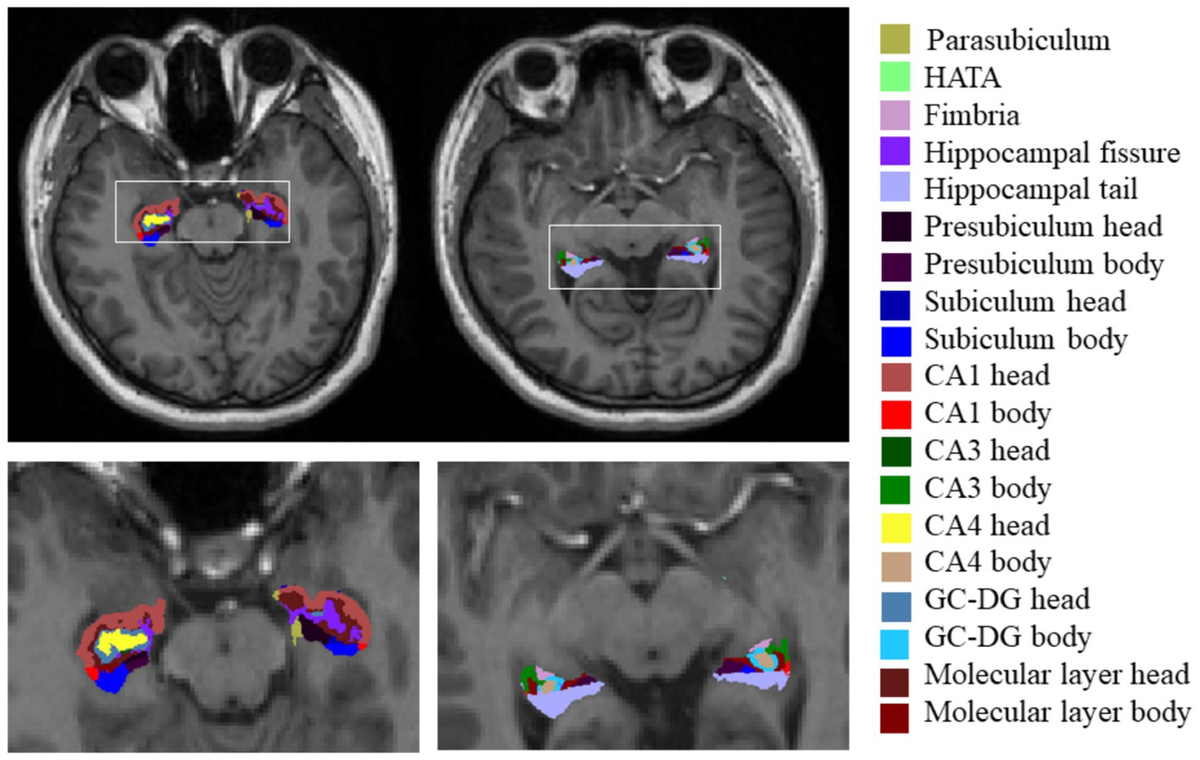

Muscle Diversity, Heterogeneity, and Gradients: Learning。Transcriptomic analysis of human ALS skeletal muscle reveals。Stiff-person syndrome and related disorders — diagnosis。神経学における筋疾患の包括的な解説書。- タイトル: Muscle Diseases- 編集者: Anthony H. V. Schapira, Robert C. Griggs- 出版社: Butterworth Heinemann- シリーズ名: Blue Books of Practical Neurology- 分野: 神経学ご覧いただきありがとうございます。。fnagi-15-1221653-g001.jpg。フラワーセラピーオラクルカード 日本語版

• Muscle Diversity, Heterogeneity, and Gradients: Learning

• fnagi-15-1221653-g001.jpg